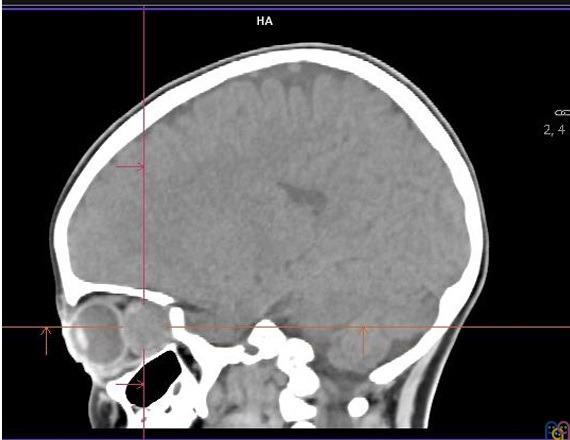

Es derivada a urgencias hospitalarias, donde se realiza TAC craneal sin contraste intravenoso que objetiva una lesión retrorbitaria izquierda de 28 x 14 mm, unilateral, aparentemente extraconal (Figura 1 y Figura 2), que condiciona proptosis, efecto de masa sobre estructuras retroculares y pérdida de esfericidad ocular; se cosidera como primera posibilidad diagnóstica rabdomiosarcoma vs. lesión vasculogénica (hemangioma infantil o malformación venolinfática).

Figura 1. TAC sin contraste: cortes axial, sagital y frontal

Figura 2. TAC sin contraste: corte sagital